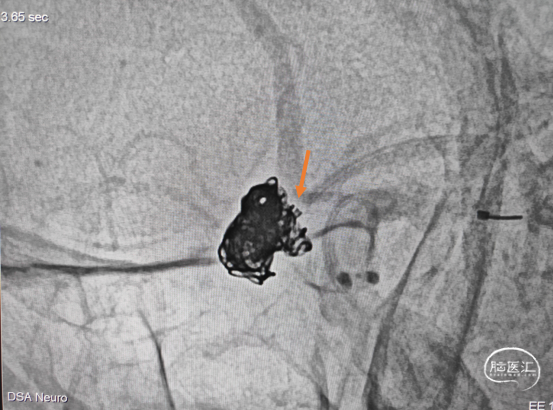

造影示瘤颈处子瘤仍显影,弹簧圈未进入子瘤,故再次用微导丝导引微导管超至子瘤口。(图示微导管头端位置)